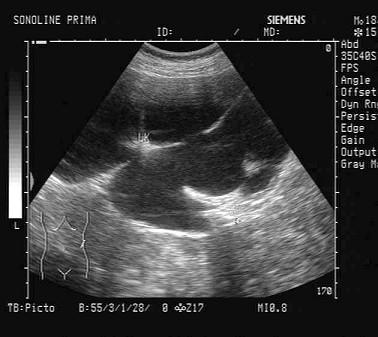

某患者左肾超声声像图如下,最可能的诊断为?(?)A.多发性肾囊肿B.肾结核C.多囊肾D.重度肾积水E.中度肾积水

选项 A.多发性肾囊肿 B.肾结核 C.多囊肾 D.重度肾积水 E.中度肾积水

答案 D